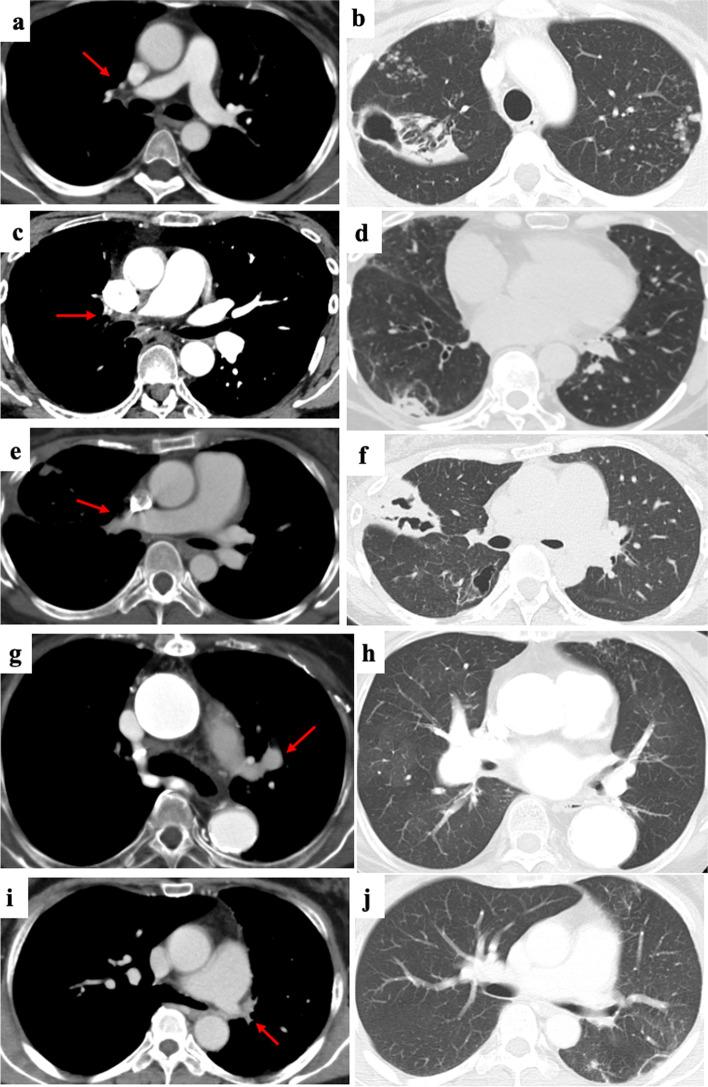

We retrospectively investigated 166 consecutive patients with TAK who attended Kyoto University Hospital from 1997 to 2018. The demographic data, clinical symptoms and signs, comorbidities, treatments, and imaging findings were compared between patients with and without PAI. TAK was diagnosed based on the American College of Rheumatology Classification Criteria (1990) or the Japanese Clinical Diagnostic Criteria (2008). PAI was identified using enhanced computed tomography, magnetic resonance imaging, or lung scintigraphy.

PAI was detected in 14.6% (n = 24) of total TAK patients. Dyspnea (25.0% vs. 8.6%; p = 0.043), pulmonary arterial hypertension (PAH) (16.7% vs. 0.0%; p < 0.001), ischemic heart disease (IHD) (29% vs. 9.3%; p = 0.018), respiratory infection (25.0% vs. 6.0%; p = 0.009), and nontuberculous mycobacteria (NTM) infection (20.8% vs. 0.8%; p < 0.001) were significantly more frequent, and renal artery stenosis (0% vs. 17%; p = 0.007) was significantly less frequent in TAK patients with PAI than in those without PAI. PAI and biologics were risk factors for NTM.